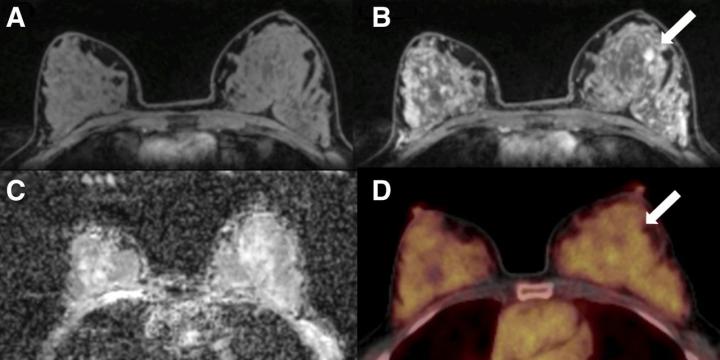

image: A 50-y-old postmenopausal woman with fibroadenoma (arrows) in left breast. (A) Unenhanced fat-saturated T1-weighted MRI shows extreme amount of FGT (ACR d). (B) Moderate BPE is seen on dynamic contrast-enhanced MRI at 90 s. (C) Mean ADC of breast parenchyma of contralateral breast on diffusion-weighted imaging with ADC mapping is 1.5 × 10?3 mm2/s. (D) On 18F-FDG PET/CT, lesion is not 18F-FDG-avid, and BPU of normal breast parenchyma is relatively high, with SUVmax of 3.2.

The study included 141 patients with imaging abnormalities on mammography or sonography on a tumor-free contralateral breast. The patients underwent combined PET/MRI of the breast with dynamic contrast-enhanced MRI, diffusion-weighted imaging (DWI) and the radiotracer 18F-FDG. In all patients, several imaging biomarkers were recorded in the tumor-free breast: background parenchymal enhancement and fibroglandular tissue (from MRI), mean apparent diffusion coefficient (from DWI) and breast parenchymal uptake (from 18F-FDG PET). Differences among the biomarkers were analyzed by two independent readers.

A total of 100 malignant and 41 benign lesions were assessed. In the contralateral breast tissue, background parenchymal enhancement and breast parenchymal uptake were decreased and differed significantly between patients with benign and malignant lesions. The difference in fibroglandular tissue approached but did not reach significance, and the mean apparent diffusion coefficient did not differ between the groups.

"Based on these results, tracer uptake of normal breast parenchyma in 18F-FDG PET might serve as another important, easily quantifiable imaging biomarker in breast cancer, similar to breast density in mammography and background parenchymal enhancement in MRI," Leithner explained. "As hybrid PET/MRI scanners are increasingly being used in clinical practice, they can simultaneously assess and monitor multiple imaging biomarkers--including breast parenchymal uptake--which could consequently contribute to risk-adapted screening and guide risk-reduction strategies."